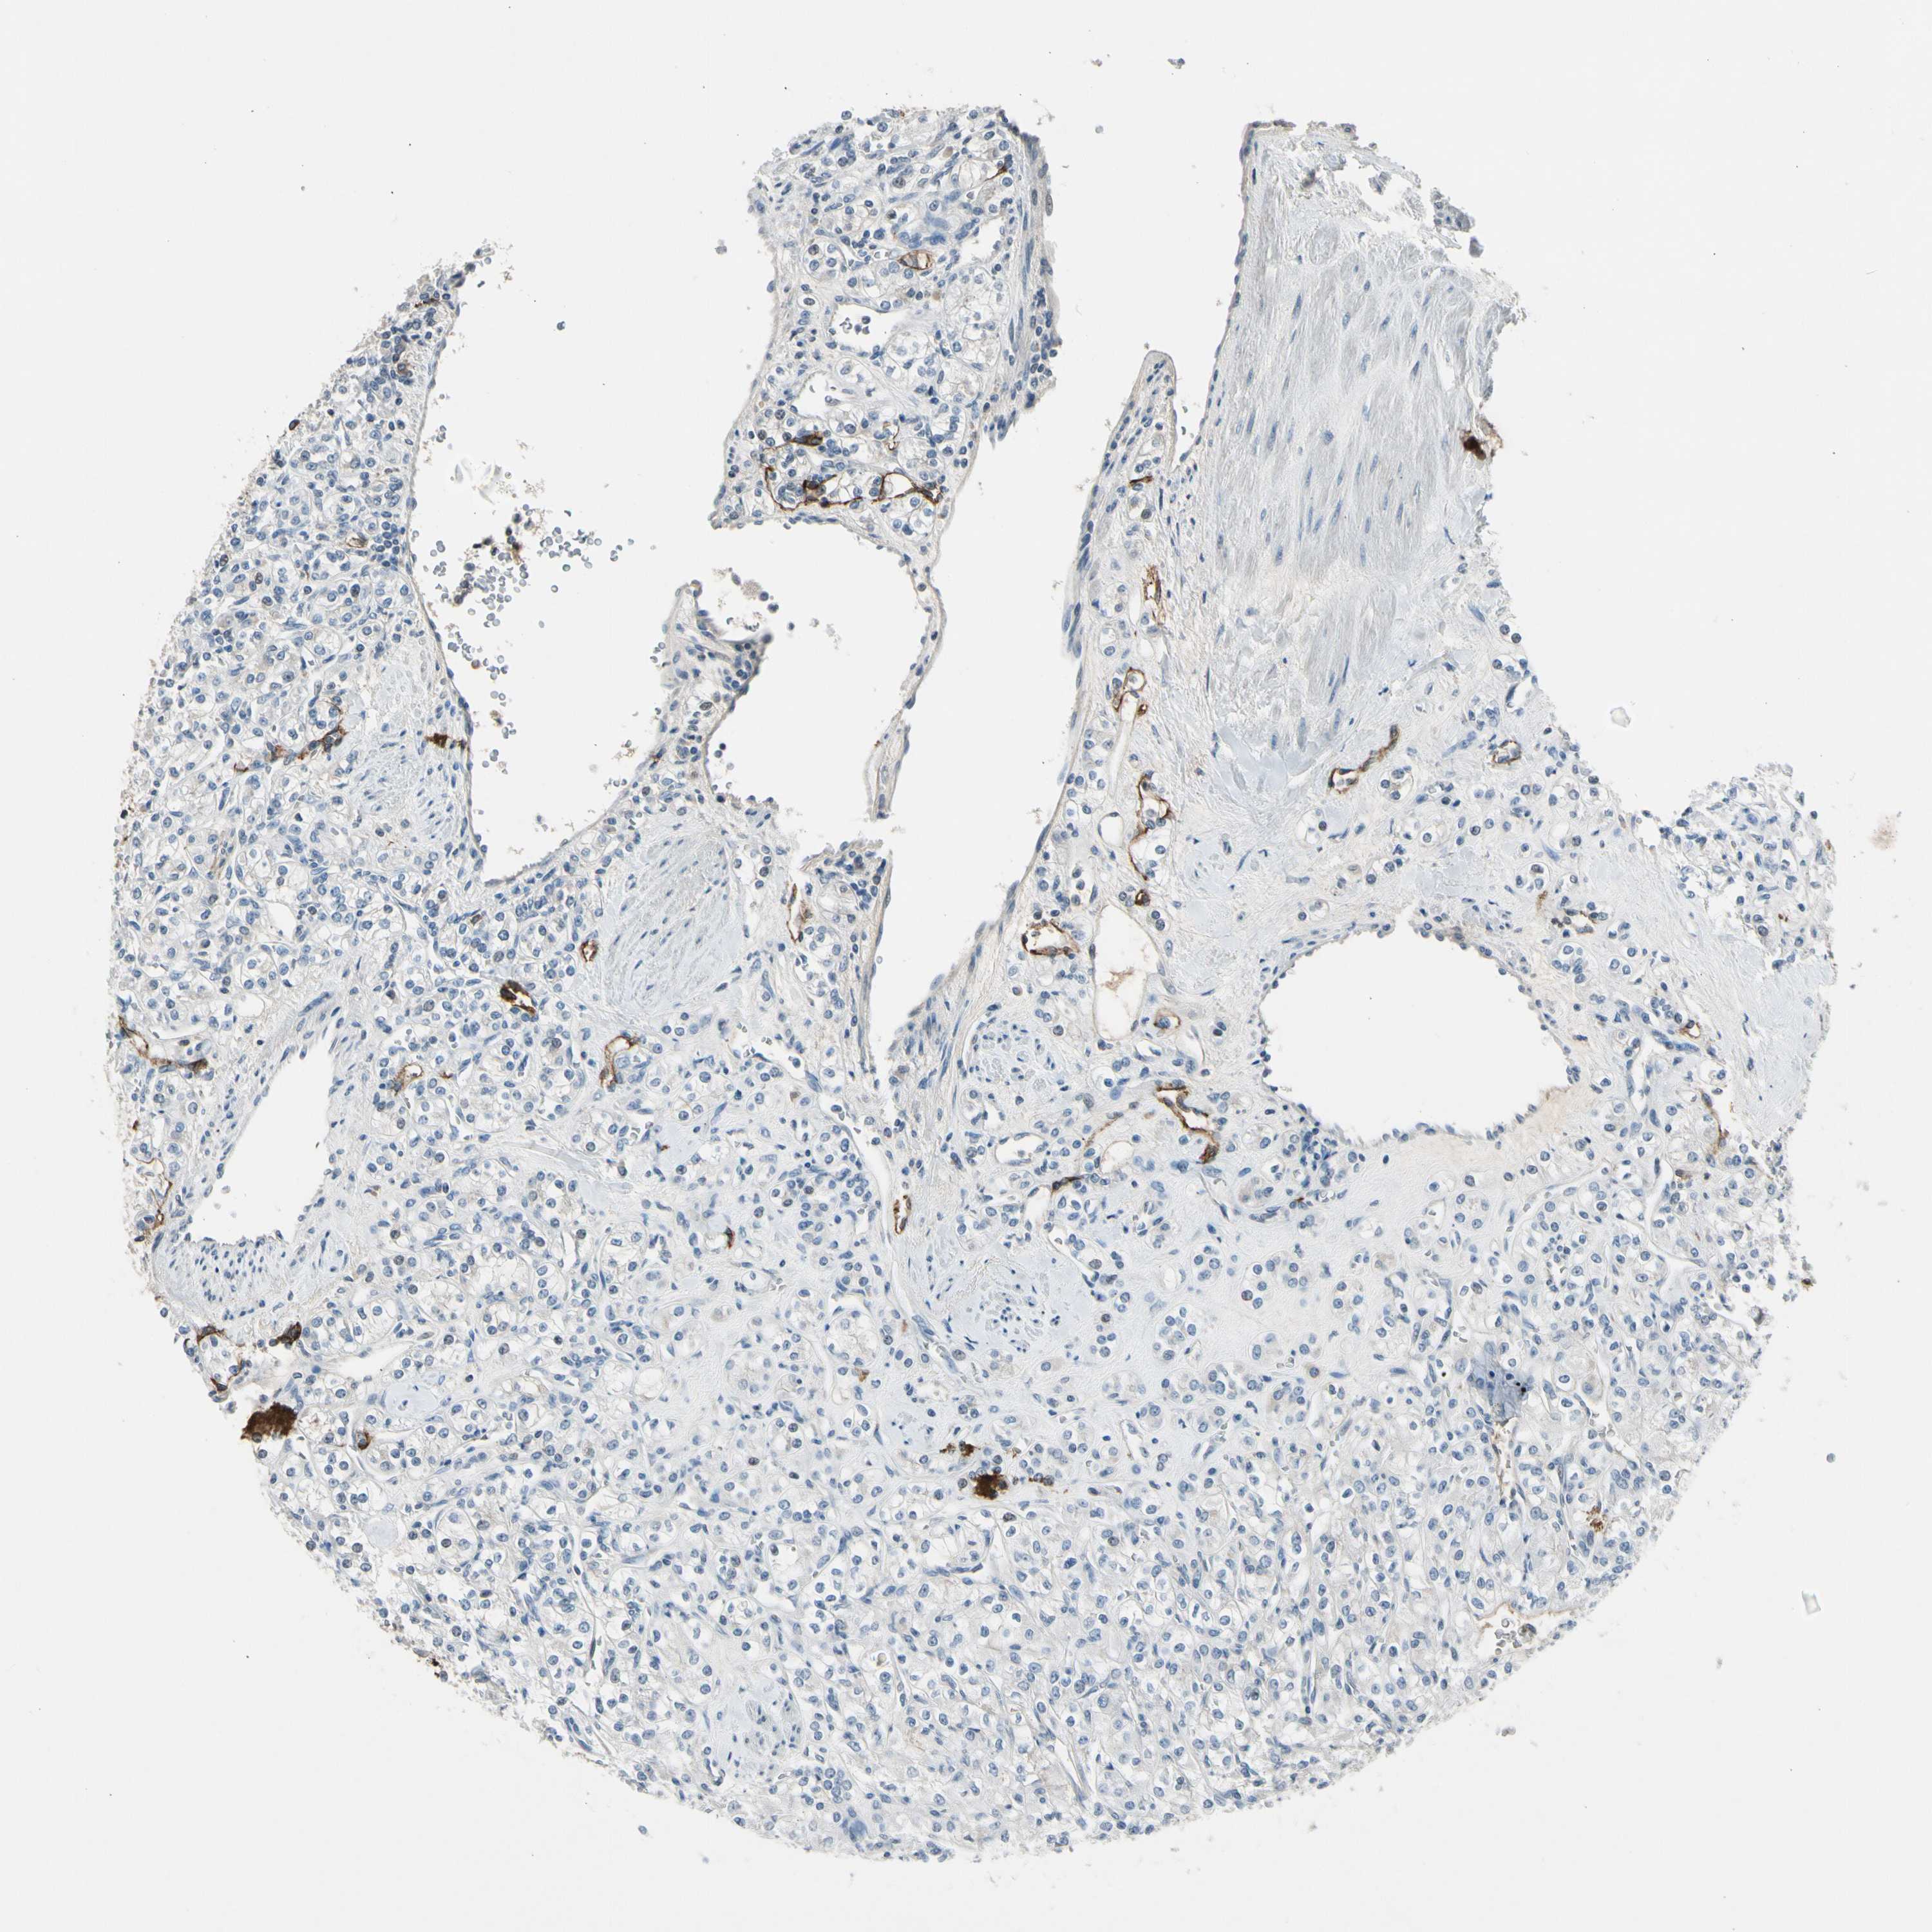

Renal cancer

Human cancer

Kidney chromophobe

Kidney renal clear cell carcinoma

Kidney renal papillary cell carcinoma